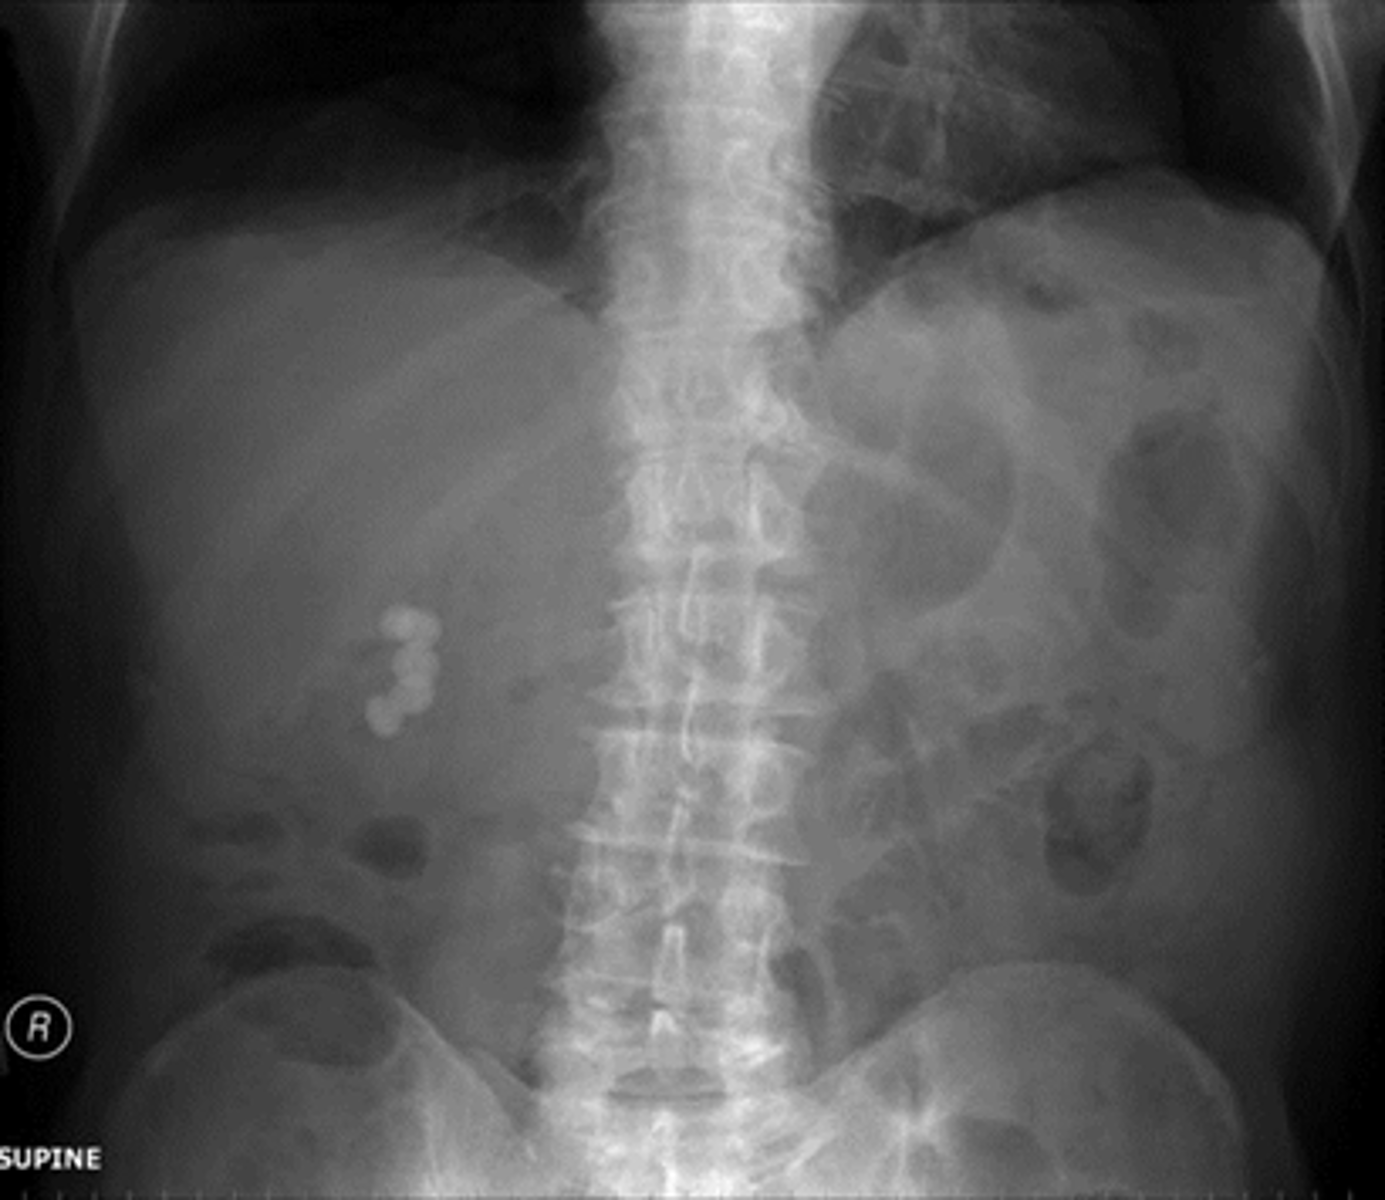

Normal supine abdomen

SOLID BLACK ARROW: small amount of air in about two or three loops of nondilated small bowel

DOTTED BLACK ARROW: air in stomach, always will have.

SOLID WHITE ARROW: air in the rectosigmoid colon.

DOTTED WHITE ARROWS: psoas muscles outlined by fat.